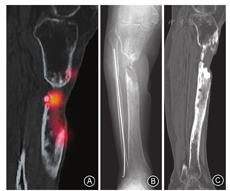

术前辅助检查是准确定位病灶的关键。常规的X线检查只能反映骨折愈合、内固定状态以及死骨的大致位置,并不能反映病灶的位置。CT可以更加细致地反映死骨片位置和病灶与周围骨组织的毗邻关系,结合核素骨显像与MR检查可以划定出病灶的大致范围。MR检查虽能准确反映髓腔内病灶波及的范围和软组织受累程度,但在合并内固定物时会出现较多的伪影,故无法作为一种常规的手段开展。近年来,核素骨显像检查在诊断骨科感染方面有很多应用,其敏感度较高,能大致判断病灶范围(图1A),但由于其特异性不高易发生误判[12],因而需要与X线(图1B)和CT(图1C)结果相结合,以在术前准确定位病灶中发挥各自优势,从而避免术中的盲目性。